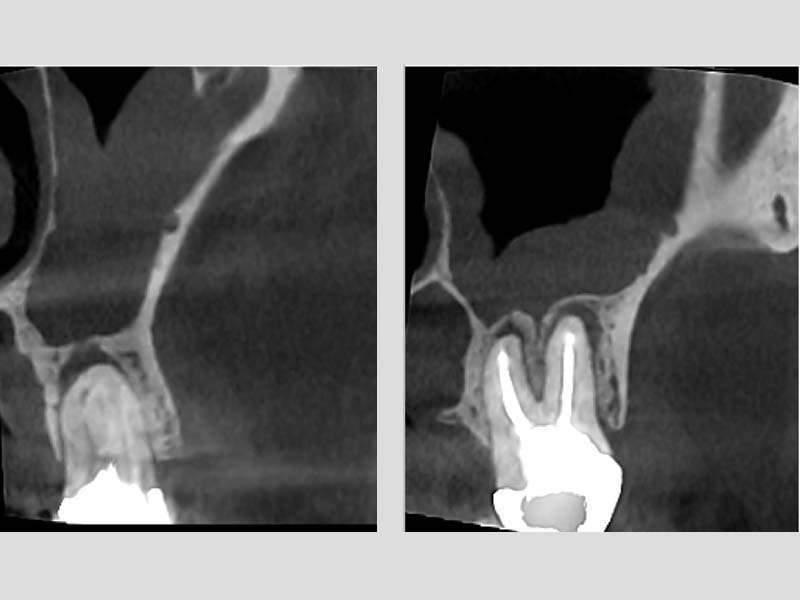

圖例為案例分享:

粉:感染增生的鼻竇黏膜

綠:原本的鼻竇範圍

紫:牙齒跟監感染,進入鼻竇

術前的電腦斷層

術後的電腦斷層,比竇黏膜已完全復原